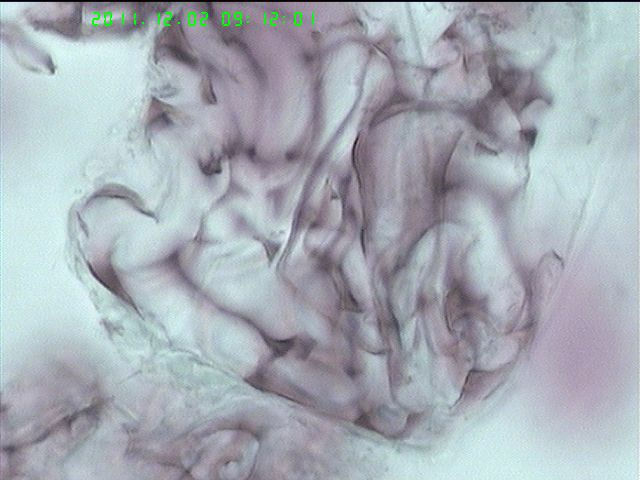

肺泡灌洗液液基

图1

浓缩的粘液。